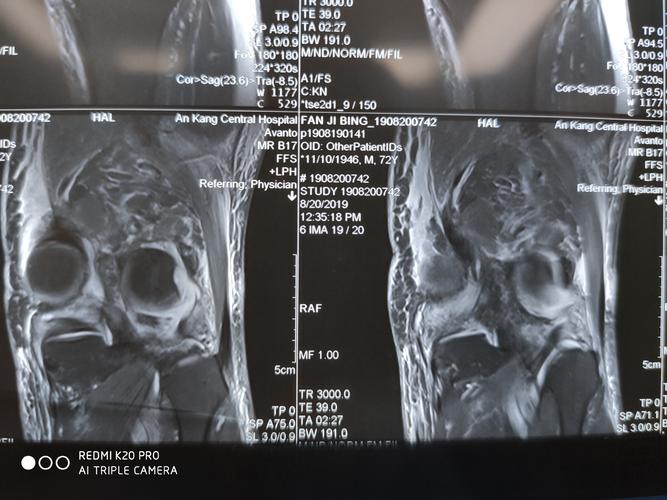

膝关节脱位,多发韧带损伤kt四型损伤一期关节镜检查后

第二天患者查的磁共振结果也出来了,患者内侧腓肠肌撕裂,腓肠肌内侧